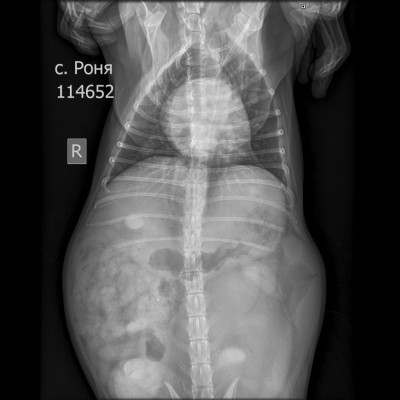

Рентген в двух проекциях и бак посев из раны

Вложения

IMG_20251130_193642_149.jpg

IMG_20251130_193646_292.jpg